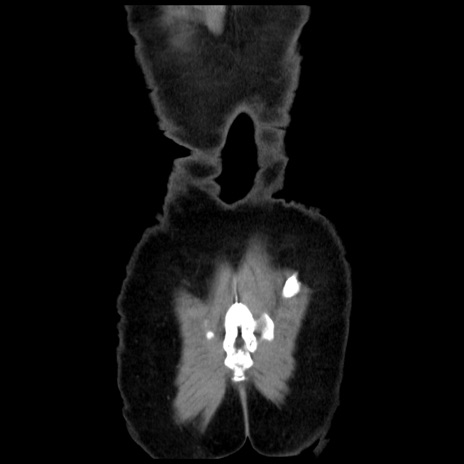

矢状断像

【症例】 50歳代女性

【主訴】 腹痛

【現病歴】前日生レバーを食べた。今朝に排便あり。 昼前に突然発症の腹痛を生じ、当院救急外来を受診した。

【既往歴】 子宮筋腫にてで子宮全摘後

【身体所見】 意識清明、腹部:平坦、軟、下腹部やや左を中心に圧痛・反跳痛あり、筋性防御あり

【データ】WBC 7800、CRP 0.07